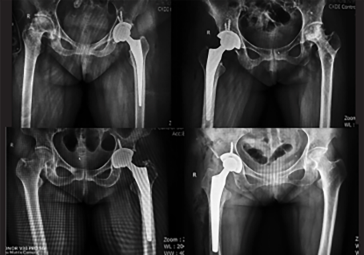

· 對CT片層進行簡單標(biāo)記后,軟件自動完成體數(shù)據(jù)的三維重建

· 支持多品牌假體選型

· 髖關(guān)節(jié)置換:髖臼+股骨雙側(cè)規(guī)劃

· 制定詳細(xì)植入計劃,術(shù)前預(yù)演